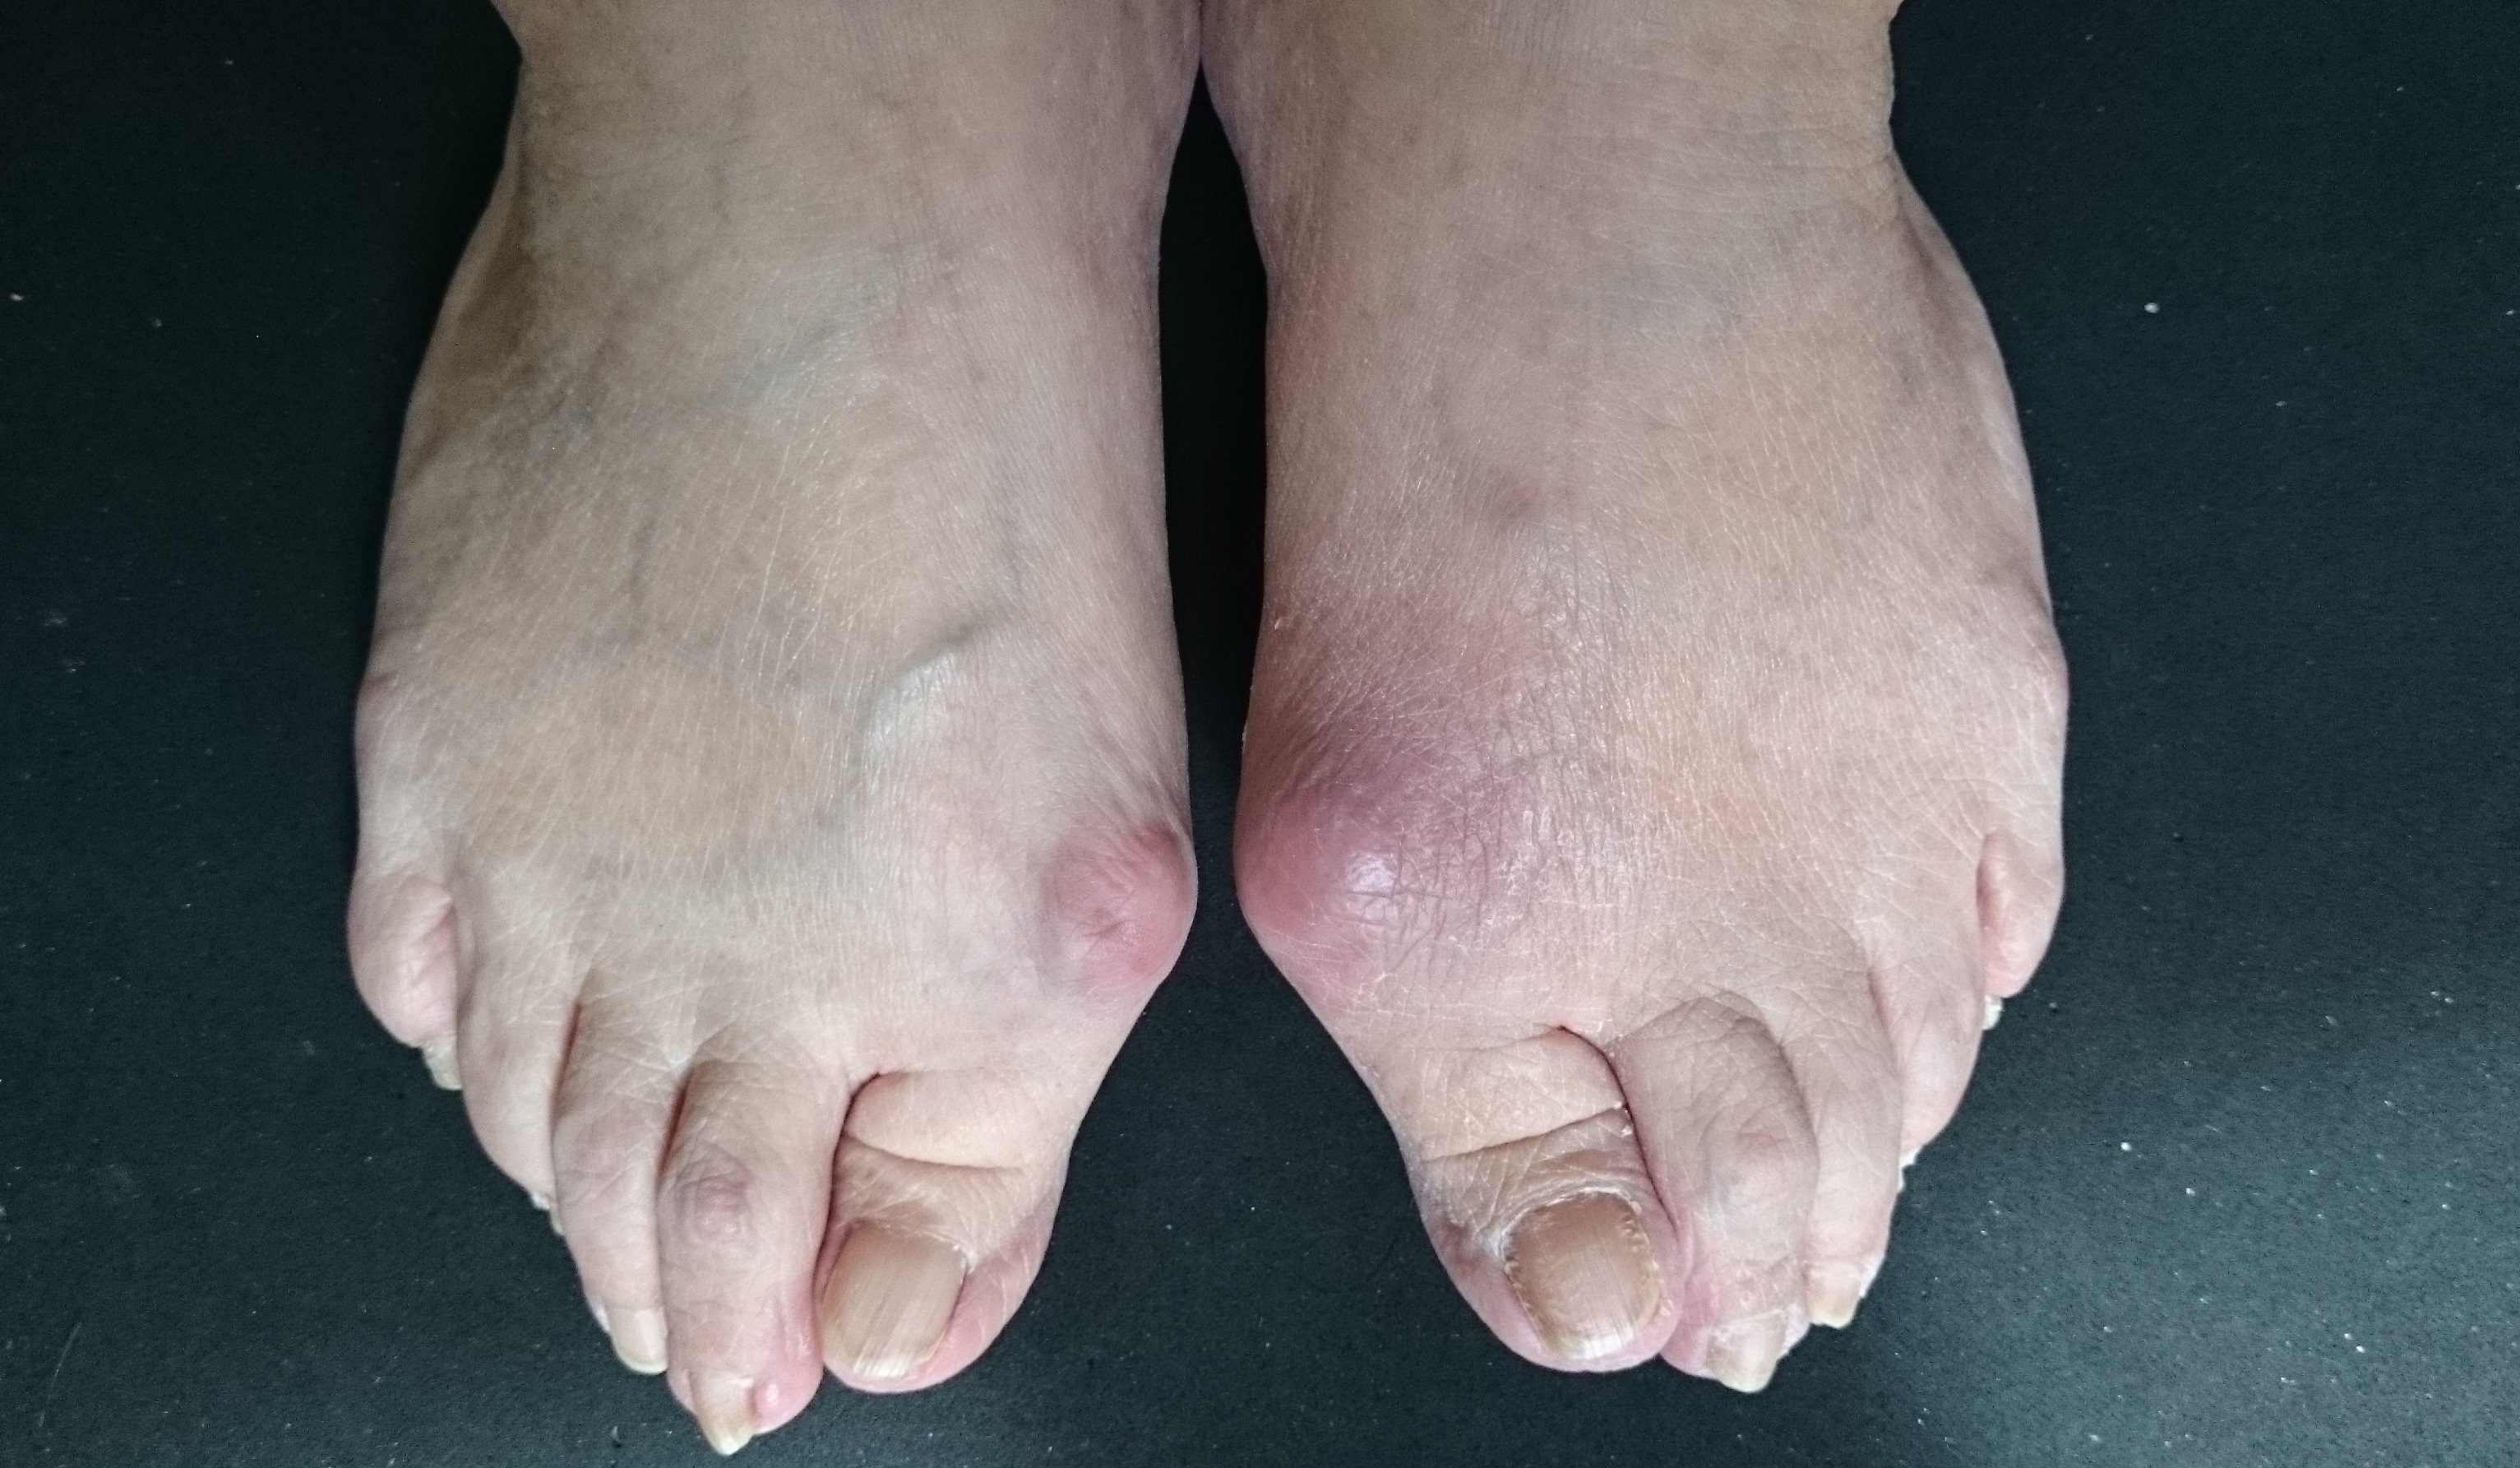

外反母趾

Hallux valgus

外反母趾用の靴として

外反母趾の痛み、変形症状の原因は靴。

原因を作らない靴で快適に痛み悪化を防ぎます。

外反母趾予防、外反母趾対策、

外反母趾対処に。

外反母趾の辛く悪化し続ける痛み、変形症状に対処

痛みを取り、悪化を防ぐ為に足に合わせるオーダーメイド靴

リウマチ・膠原病

Rheumatism

リウマチ、膠原病は不可抗力なご病気。

リウマチの90パーセントは女性が発症

靴が合わない事は勿論、

足が入らない変形と歩行困難などでお困りの方ご相談ください。

リウマチ、膠原病など、靴にお困りの方に足に合う靴、歩行を助けるための靴などご相談に応じます。